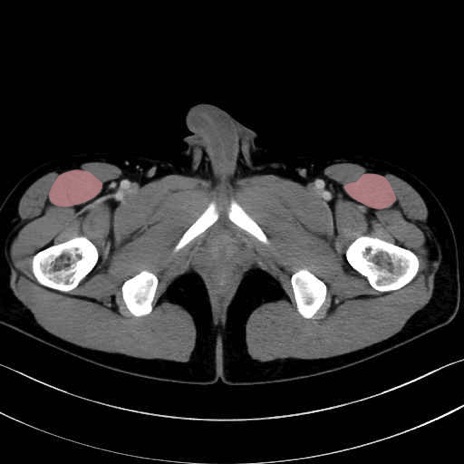

4. 深層外旋六筋(股関節の深部)

梨状筋 (Piriformis)

内閉鎖筋 (Obturator internus)

外閉鎖筋 (Obturator externus)

大腿方形筋 (Quadratus femoris)

5. 大腿前面(大腿四頭筋群・伸筋群)

縫工筋 (Sartorius)